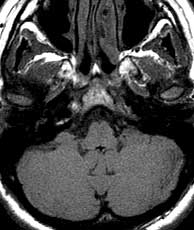

PDW & T2 ax